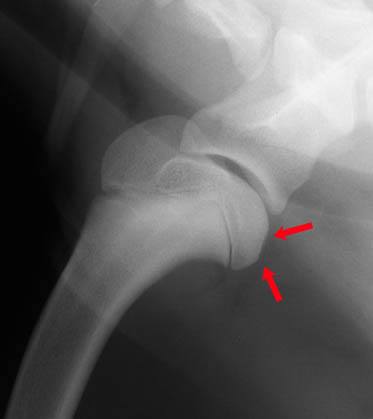

Cette carte de concepts créée avec IHMC CmapTools traite de: Ostéochondrite-dissécante-Roxanne, ∘ Examen externe : où l'on recherche Une limitation des amplitudes d'extension et de flexion, due à la douleur, ∘ Traitement chirurgical : Curetage de la lésion, Les chiens en croissance entre 4 et 10mois, en particulier les mâles. Tels que Rottweiler, ∘ Examen externe : où l'on recherche Une boiterie qui s'aggrave à l'effort, Les chiens en croissance entre 4 et 10mois, en particulier les mâles. Tels que Golden retriever, ∘ Examens complémentaires : Ponction articulaire → Afin d'exclure l'arthrite, ∘ Examen externe : où l'on recherche Un épanchements et des crépitements articulaires, Les chiens en croissance entre 4 et 10mois, en particulier les mâles. Tels que Berger allemand, Les chiens en croissance entre 4 et 10mois, en particulier les mâles. Tels que Labrador, Ostéochondrite dissécante entraîne Ostéite + Synovite, Les chiens en croissance entre 4 et 10mois, en particulier les mâles. Tels que Setter, ∘ Traitement chirurgical : Extraction des fragments cartillagineux, ∘ Examens complémentaires : Radiographie → Afin d'exclure la fracture → Recherche de lésions d'OCD